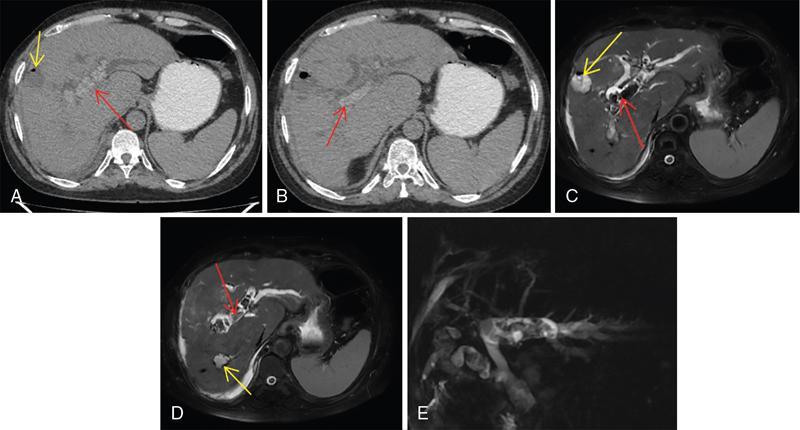

Ritu K. Kashikar, Shrinivas B. Desai, Chandresh Karnavat, Nilesh Doctor The biliary tract is subject to a variety of abnormalities. The spectrum includes benign diseases of autoimmune, infective, ischaemic, infiltrative aetiologies and malignant disorder, which most importantly represents cholangiocarcinoma. Imaging in particular magnetic resonance cholangiopancreatography (MRCP) plays a vital role in diagnosis and follow-up of these disorders. Multidetector computed tomography (MDCT) and magnetic resonance imaging (MRI) are also crucial in preoperative staging of biliary malignancies and making decisions regarding resectability and extent of resection. This chapter focuses on important benign and malignant disorders of the biliary tree and imaging features that aid in differentiation of various entities. A variety of disorders affect the biliary tree. Most biliary disorders manifest as biliary dilatation. The various causes are listed in Table 9.15.1. Imaging plays an important role in identification of aetiology based on pattern of involvement in association with clinical picture. USG is often the first investigation in a patient with jaundice. USG is excellent at showing biliary dilatation. It may be useless in assessing level of obstruction and biliary stones. Changes in liver morphology, development of cirrhosis is accurately done on USG. Early changes in conditions like primary sclerosing cholangitis (PSC), presence of intrahepatic ductal strictures, thickening of common bile duct (CBD) are, however, not confidently seen and need imaging modalities like MRCP and computed tomography (CT). Staging of hilar cancers is also best done on CT or MRI with contrast. Contrast-enhanced CT is extremely accurate in staging hilar cancers. It is a preferred modality to access radial spread of the disease and vascular involvement. Subtle changes of PSC and autoimmune cholangitis may however be missed and MRCP is preferred in these conditions. The protocol for evaluating biliary disease is standard plain scan followed by early, late arterial, portal venous and parenchymal phases similar to that obtained for focal liver lesions. Delayed phase images should be obtained for hilar malignancies, which often show delayed enhancement. MRCP with or without contrast is the modality of choice in diagnosing and characterizing biliary diseases. Owing to its noninvasive nature, it has replaced endoscopic retrograde cholangiopancreatography (ERCP) in the initial evaluation and follow-up of a variety of biliary pathologies. Absence of radiation exposure makes it suitable to obtain follow-ups in patients requiring serial scanning. The ability to diagnose abnormalities of both intra- and extrahepatic biliary tree, level of obstruction, longitudinal and radial spread of neoplastic process make it an ideal modality. MRCP protocol includes T2 weighted single-shot fast spin-echo, T1 weighted in phase and opposed phase gradient echo, diffusion-weighted imaging, T2-weighted fat-suppressed fast spin-echo in axial and coronal. A pre contrast three-dimensional T1-weighted fat-suppressed spoiled gradient-echo image is obtained in addition to 3-D MRCP. Postcontrast protocol includes dynamic three-dimensional T1-weighted fat-suppressed spoiled gradient-echo (in arterial, late arterial and portal venous, parenchymal and delayed phases). Since the advent and widespread use of MRCP, the utility of ERCP in diagnosing biliary pathologies has significantly reduced. ERCP is primarily used when stenting or other procedures need to be performed in the same setting. Although an invasive procedure with postprocedural risk of pancreatitis ERCP allows excellent depiction of biliary changes in conditions like PSC, recurrent pyogenic cholangitis (RPC) and IgG4-related disorders. Endoscopic USG (EUS) is an excellent modality in diagnosing lower bile duct pathologies and also has the added advantage of obtaining a biopsy in the same setting. EUS is less invasive than ERCP and overall safer. PSC is a premalignant cholestatic liver disorder characterized by bile duct strictures secondary to bile duct inflammation and fibrosis. Cirrhosis of liver can develop secondary to this condition and patients are at a high risk for biliary and colonic cancers. PSC is a relatively rare disease, with an incidence of less than 50 per 100,000 patients though it varies in various location. It is diagnosed in young patients aged 30–40 years and is twice as common in men than in women. Similar to other autoimmune diseases, genetic susceptibility is likely to be instrumental in the development of PSC after exposure to a trigger. There is also a strong association between PSC and human leukocyte antigens (HLAs). Environmental factors such as childhood microbial exposure also play an important role in disease pathogenesis. A strong association of PSC with inflammatory bowel disease (IBD) is seen. There is a 100-fold increased risk of developing PSC among siblings. PSC can be asymptomatic but may present with cholestatic symptoms such as jaundice, pruritus, fatigue and right upper quadrant pain, steatorrhoea and episodes of acute bacterial cholangitis. There is marked elevation of alkaline phosphatase (ALP). A twofold to threefold increase in serum alanine and aspartate aminotransferase (AST) can be seen. Elevated bilirubin is usually seen in advanced disease, malignancy or those with choledocholithiasis. Various serum antibodies can also be elevated in PSC. These have been enlisted in Table 9.15.2. On liver biopsy, classic pathologic features of periductal concentric fibrosis or ‘onion skin’, around the affected ducts can be seen. This is however not a pathognomonic finding and is seen in less than 40% of biopsy specimens. Therefore, biopsy is not routinely used as a diagnostic tool for PSC and is reserved primarily for disease staging. MRI with MRCP best depicts the biliary changes in PSC and is the modality of choice. While CT and USG may show biliary dilatation and changes of cirrhosis in advanced cases, they fail to show early changes (Table 9.15.3). USG is an effective modality for the visualization of dilatation and diffuse wall thickening of the extrahepatic bile duct. Other feature seen on USG is bright echogenic portal triad. However, the role of USG in the diagnosis of early PSC is limited owing to suboptimal assessment of the intrahepatic biliary ducts. Features of advanced disease such as heterogeneous coarse echogenicity can be readily detected with USG. The major benefit of performing US is to guide liver biopsy. Also, liver stiffness as assessed by transient elastography correlated well with the degree of liver fibrosis in PSC patients. CT can demonstrate some findings suggestive of sclerosing cholangitis such as focal, discontinuous, often peripheral intrahepatic biliary duct dilatation and thickening with enhancement of the bile ducts owing to inflammation. CT is effective in helping exclude other causes that can result in biliary stasis and dilatation such as hepatic and pancreatic lesions. CT is also excellent in diagnosing tumours, which may sometimes have similar presentation. Concomitant changes of IBD, if present, can be seen. However, CT is limited in assessment of biliary strictures and visualization of disease involving small peripheral bile duct, especially in the early stages of the disease. CT shows changes of cirrhosis in liver and assessing changes of portal hypertension. MRCP is diagnostic imaging modality of choice in the workup of patients with suspected PSC, as recommended by both the AASLD and EASL guidelines. MRCP has high diagnostic sensitivity (86%) and specificity (94%) for the detection of PSC (Table 9.15.3). Multifocal short segmental strictures in the intra- or extrahepatic biliary tree with intervening normal or dilated duct leading to beaded appearance are seen in early disease. The location in strictures is usually at the biliary bifurcation and are disproportionate to upstream dilatation. Advanced cases show pruning of peripheral biliary radicals secondary to advancing fibrosis obliterating the smaller ducts. An obtuse angle between the central and peripheral ducts is suggestive of PSC. Diverticula and webs also can be seen, though not pathognomonic (Table 9.15.4) (Figs. 9.15.1–9.15.3). Strictures of the CBD of less than 1.5 mm and of left, right or common hepatic duct (CHD) of less than 1 mm are defined as dominant stricture. A dominant stricture is associated with worse prognosis in part due to development of cholangiocarcinoma. MRCP plays an important role in raising the suspicion and guiding treatment. A dominant stricture may be confused with hilar cholangiocarcinoma on imaging and it is often impossible to distinguish the two based on imaging alone (Table 9.15.4) (Fig. 9.15.4). Changes in liver morphology are seen in the form of distortion. The classical change described in PSC includes hypertrophy of the caudate lobe and atrophy of the left lateral and right posterior segments of the liver. Hypertrophy of caudate lobe is more frequent in PSC than cirrhosis from other aetiologies. Other parenchymal changes include heterogeneity of liver, periportal cuffing, peripheral inflammation, cirrhosis and features of portal hypertension. Hyperintensity of the liver parenchyma in PSC on nonenhanced T1-weighted images has been reported. Wedge-shaped peripheral atrophic areas of confluent hepatic fibrosis are seen as high T2-weighted signal intensity. Periportal oedema is visualized as high signal intensity in periportal region on T2-weighted. Increased heterogeneous peripheral enhancement of the liver parenchyma can be seen and is likely due to the altered blood supply in those areas in response to parenchymal inflammation (Table 9.15.4) (Figs. 9.15.5 and 9.15.6). MR elastography is the most accurate noninvasive method for the diagnosis and staging of liver fibrosis and could potentially replace liver biopsy. It is predictive of progression to decompensated liver disease. However, lack of wide availability are still major limiting factors. MR elastography is not influenced by obesity or anatomical conditions (e.g. narrow intercostal spaces and ascites) and the sample size of the liver is significantly higher and hence has several advantages over ultrasound elastography (Table 9.15.5). Besides these features, enlarged reactive abdominal lymph nodes, commonly periportal and portocaval lymph nodes, are commonly diagnosed in PSC and should not be misdiagnosed as a lymphoproliferative disorder or metastatic disease. Though ERCP has higher diagnostic accuracy in detecting PSC, its role is limited to intervention required in PSC due to its invasive nature and potential complications. Also it is recommended that MRCP be performed prior to ERCP as a preprocedural MRCP can provide a road map to the endoscopist. Small duct PSC is a variant PSC syndrome with biochemical markers and histologic features suggestive of PSC with normal cholangiography. It is associated with better prognosis. Approximately one-fourth of patients’ progress to classic PSC in an average of 8 years. Bile duct calculi are a common complication of PSC. Pigmented bile duct stones are common owing to biliary stasis. Both intrahepatic and extrahepatic biliary stones can be found. However, the presence of biliary tree stones is not an essential diagnostic feature. Soft calcific foci within dilated bile ducts can be seen on US and CT images. MRI with MRCP is the imaging modality of choice to detect bile duct stones and appear as focal areas of signal-intensity-void filling defects on T2-weighted images. Usually isointense at T1-weighted imaging but frequently are hyperintense. The presence of biliary strictures puts these patients at risk of bacterial cholangitis in PSC patients. The classic Charcot triad of fever, abdominal pain and jaundice can be seen. Early enhancement of the biliary wall due to the biliary duct inflammation is a common finding with peribiliary reactive hepatic parenchymal changes. Cholangitic abscesses may sometimes be seen. PSC patients are at high risk of developing cholangiocarcinoma during the disease course with and a total risk of 10%–15%. Approximately 30% of all cholangiocarcinomas are detected within the first year of establishing a diagnosis of PSC and so it is important to be suspicious even at the time of PSC diagnosis and to survey for early detection. Rapid clinical deterioration, worsening of jaundice, pruritus, weight loss along with elevation in serum bilirubin and ALP should raise suspicion of PSC. It may be difficult to distinguish benign from malignant strictures. Progressive bile duct wall thickening, irregularity, enhancement, new onset biliary dilatation, dominant stricture or development of focal strictures with dilatation and ipsilateral atrophy are indeterminate features that may raise possibility if occult cholangiocarcinomas. Perivascular thickening, vascular involvement or occlusion are features favouring malignancy. Definite diagnosis is however often not possible on imaging alone and a brush biopsy should be taken in patients with new onset clinical symptoms, elevated tumour makers or above-mentioned indeterminate imaging features (Table 9.15.7). The most common subtype of cholangiocarcinoma in PSC patients is periductal type, characterized by long segment irregular wall thickening along the bile duct with no identifiable mass. The lesion is hypointense on T1W1 images and hyperintense on T2W1 images showing progressive enhancement on contrast study. The tumour could be at the bifurcation and can cause abrupt cut-off, commonly presenting as Klatskin tumour (Fig. 9.15.7). Combined UC and PSC is associated with a higher risk for colorectal carcinoma than UC alone. PSC is considered as an independent risk factor for development of colorectal carcinoma in patients with UC. Malignancy tends to involve the right colon or more proximal parts of the colon. Clinical presentation and history in patients with ascending cholangitis differ from those with PSC. Fever, pain and jaundice dominate the presentation in patients with ascending cholangitis while patients with PSC may be asymptomatic. The typical findings of PSC including biliary duct stenosis, beading or pruning are not typical findings in the newly diagnosed cases of acute ascending cholangitis. Wedge-shaped peripheral and/or intrahepatic peribiliary foci of increased T2 signal around the dilated radicals with arterial and/or delayed parenchymal enhancement has been described in ascending cholangitis. Patients with RPC present with recurrent episodes of abdominal pain, fever, jaundice and chills. These features differ from those in patients with PSC. Hepatolithiasis with pigmented stones in the biliary tree and upstream and downstream duct dilatation are typical imaging features in RPC (Table 9.15.8). Ischaemic cholangiopathy is a form of biliary injury resulting from decreased arterial supply. History of liver transplantation is the key in diagnosing ischaemic cholangiopathy. Biliary strictures in AIDS cholangiopathy are indistinguishable from PSC. However, the combination of papillary stenosis and intrahepatic ductal strictures appears relatively unique to AIDS cholangiopathy; this combination is not found in PSC. Clinical history may help to distinguish one from the other. Effective medical therapy for PSC is lacking. Oral ursodiol (ursodeoxycholic acid) is one of the main treatment options of cholestatic diseases though does not prevent disease progression. Azathioprine and steroids are recommended for use in patients with AIH as well as those with AIH–PSC overlap syndrome. Vedolizumab is a gut-specific monoclonal antibody that has been tried but the clinical utility in PSC–IBD patients remains under investigation. Dilatation of biliary strictures, stenting, lithotripsy and stone extraction can be done with the aid of ERCP and percutaneous transhepatic cholangiography (PTC). The only definitive cure of PSC is, however, liver transplantation. Treatment of complications like choledocholithiasis stone removal can be accomplished by using standard endoscopic techniques with or without sphincterotomy, with balloon or basket extraction for extrahepatic biliary stones. For bacterial cholangitis, immediate administration of broad-spectrum antibiotic therapy is recommended and in abscess formation percutaneous drainage with intravenous antibiotic therapy shows favourable outcome compared with surgical drainage. Incidence is 20%–25%. Diagnosis of recurrent PSC requires careful evaluation, as there are other causes of biliary changes after liver transplant with similar features. Nonanastomotic biliary strictures imply the diagnosis of recurrent PSC only if they occur more than 90 days after transplant. Characteristic multifocal strictures and segmental dilatations of biliary ducts are suggestive findings. MRCP is the initial modality. RPC is characterized by a triad of recurrent biliary sepsis, inflammatory biliary strictures and intrahepatic stones. Fifty per cent of patients may have acute pancreatitis. Oriental cholangiohepatitis, primary hepatolithiasis, Hong Kong disease and oriental infestational cholangitis. Prevalence in the third and fourth decades of life with equal frequency among men and women peak. Southeast Asia predominantly in rural population and in lower socioeconomic groups. Gut-derived organisms lead to sepsis, which initiates a cascade of events, which leads to a chronic, progressive and recurrent inflammatory process in cholangioles. Associations with Clonorchis sinensis, Opisthorchis species, Fasciola hepatica and Ascaris lumbricoides infestations have been suggested. Common organisms cultured from bile include Escherichia coli, Klebsiella, Pseudomonas and Proteus species and anaerobes. Structural biliary abnormalities may develop before stones are demonstrable. Strictures may be seen at cholangiography without stones and vice versa. Entrapped stones cause stasis, sepsis, scarring and stricturing with the increasing lithogenicity (Table 9.15.9). Typically present with abdominal pain, fever and jaundice (the Charcot triad) and commonly provide history of repeated episodes. Routine investigations may demonstrate leukocytosis, deranged liver enzymes with obstructive pattern. Elevated cholestatic markers (bilirubin, ALP and gamma GT) and deranged LFTs can be seen. Serum inflammatory markers can be elevated. Additional tests aiding in differential diagnosis include autoantibodies, ANCA, CA19-9 and serologic tests for Echinococcus. Histology is usually not required. It shows fibrous mural thickening of bile ducts and periductal tissue, as well as acute and chronic inflammatory changes. The imaging features include changes in bile ducts, development of calculi and changes in the parenchyma. The disease affects intrahepatic ducts more than the CHD and CBD. Disproportional dilatation of central intrahepatic ducts and extrahepatic bile ducts is seen with nondilated or minimally dilated peripheral ducts, leading to abrupt tapering of bile ducts. All segments of biliary tree may be involved, but the lateral segment of the left lobe is most often and extensively involved most likely because left hepatic ducts come off at a more acute angle compared with the right hepatic ducts, thus predisposing to stasis and stricture formation (Table 9.15.10). Hepatolithiasis is common in patients with RPC. Stones are composed mainly of bile pigments with variable calcification. There may be single or multiple stones scattered in the intra- or extrahepatic ducts or both. The dilatation of the extrahepatic duct is generally not related to the location of the stone. Ducts both proximal and distal to the stone are dilated. Parenchymal atrophy most commonly involves the left lateral and right posterior segments while hypertrophy of the caudate and right lobe is seen. USG shows dilatation of the central intrahepatic and extrahepatic ducts, with relative sparing of the peripheral biliary tree. Hepatolithiasis can be seen in 90% of cases. The echogenicity and acoustic shadowing of calculi may vary depending on extent of calcification. There is often associated periportal echogenicity. Ultrasound may be useful in performing image-guided percutaneous drainage of abscesses or biopsy of suspicious lesions. Limitations include inability to detect subtle intrahepatic ductal dilatation and heavy stone burden obscuring evaluation of underlying hepatic parenchyma. Contrast-enhanced CT is increasingly being used as first line of imaging. It allows for detection of characteristic disproportionate dilatation of the extrahepatic and central intrahepatic ducts. Contrast-enhanced CT also allows for detection of bile duct wall enhancement, suggestive of acute cholangitis. Ninety per cent stones are hyperdense to liver parenchyma on nonenhanced scan. Extent of calcification in calculi may vary. Parenchymal atrophy affects left lateral segment most frequently, followed by right posterior segments. Eventually, changes of cirrhosis can be seen. Heterogeneous appearance of liver parenchyma with segmental steatosis and altered enhancement can be seen particularly during acute attack. Pneumobilia is not infrequent and can usually be attributed to recent procedures or surgeries like bilioenteric anastomosis. It may, however, be seen in patients without history of prior interventions due to recent passage of stone through the ampulla or less commonly cholangitis related to gas forming organisms (Fig. 9.15.8). Subtle intrahepatic ductal strictures and noncalcified stones may be missed on CT. MRCP allows visualization of both intra- and extraductal disease and can reveal complete extent, severity and complications of the disease. Even noncalcified calculi which may be missed on CT or sonography, are seen as intraductal filling defects on heavily T2-weighted images and may appear hyperintense to the liver on T1-weighted images. MRI demonstrates central and extrahepatic duct dilatation with decreased arborization and abrupt tapering of peripheral ducts. MRI particularly MRCP sequences accurately depicts stenotic segments and delineates the entire biliary tree, including the proximal part of the stricture, without risk of aggravating biliary sepsis. Even short segment duct strictures <1 cm are easily seen on MRCP (Figs. 9.15.8 and 9.15.9). Parenchymal abnormalities like hepatic atrophy, whether diffuse or segmental, and altered signal can be accurately diagnosed. Mass lesions and hepatic abscesses, if present, are also well delineated. The characteristic finding of disproportionate dilatation of the ducts, with multiple intraductal calculi are well demonstrated. There may also be intrahepatic strictures, with abrupt tapering of the peripheral ducts as well as decreased arborization of the biliary tree (arrowhead appearance). It allows for better spatial resolution, thus permitting better evaluation of the smaller peripheral ducts. The main limitation of ERCP is its invasive nature, with complications such as ERCP-associated pancreatitis. Heterogeneous parenchymal enhancement, wall thickening and periductal enhancement are seen in acute cholangitis. Abscess formation is encountered in up to 20% of RPC patients who undergo cross-sectional imaging. The abscesses can occur in both the affected and unaffected portions of the liver but most commonly seen in the right lobe. Sonography guided aspiration can be done when diagnosis is doubtful. Intrahepatic bile lakes are not infrequent and may or may not communicate with the biliary tree. On USG bilomas appear anechoic and are usually hypodense on CT with or without calculi. Leakage of bile from a severely dilated obstructed duct may lead to formation of extrahepatic biloma. Cholangiocarcinoma is the most feared complication and may be seen in up to 5% of patients. Segments with high stone burden or those with atrophy are more prone to developing cholangiocarcinoma. Clinical and laboratory indicators for development of cholangiocarcinoma in patients with PSC include increase in jaundice without associated cholangitis, sudden weight loss, significant elevation of ALP and rising tumour markers. Peripheral cholangiocarcinoma manifests as expansion of the affected segment. Hypoattenuating mass with showing peripheral enhancement causing narrowing of the portal vein may raise suspicion of malignancy. Portal vein thrombosis has also been reported but is rare. Recurrent biliary sepsis may lead to periductal inflammation and portal thrombophlebitis. Portal thrombosis can lead to lobar atrophy with compensatory hypertrophy of the uninvolved lobe. Higher incidence of hepatocellular carcinoma (HCC) is reported in patients with RPC due to development of cirrhosis in severe cases. Management should comprise antibiotic treatment, clearance of stones, maintenance of biliary drainage and long-term follow-ups. ERCP allows for therapeutic procedures such as stone removal and stenting of strictures. Destroyed liver segments, those with multiple abscesses and patients with secondary cholangiocarcinoma are candidates or surgery. Stone extraction can also be done surgically with the aid of basket, forceps, balloon catheter or flexible choledochoscope. Transduodenal sphincteroplasty and hepaticojejunostomy are commonly performed drainage procedures. Indications for transplantation include extensive bilobar hepatolithiasis, cirrhosis and liver failure. IgG4 cholangiopathy is a cholangitis characterized by elevated serum IgG4 and infiltration of the bile duct wall with IgG4 positive plasma cells leading to storiform fibrosis and obliterative phlebitis with resultant bile duct wall thickening. This condition shows good response to steroids. Frequent association with IgG4-related autoimmune pancreatitis is seen. IgG4 sclerosing cholangitis (IgG4-SC) has a threefold to fivefold higher prevalence in men than women. It usually presents in the fifth and sixth decades of life. Incidence of this disease is approximated to be around 0.28–1.08/100,000. Autoimmunity has been considered as the most probable pathogenesis of IgG4-related disease (IgG4-RD). Several HLA association have identified as determinants of disease susceptibility. The major histologic features associated with IgG4-RD have been well described and include the steps. Chronic or recurrent cholangitis is the most common presentation and seen in up to 75% cases. Other symptoms seen are fever, pruritus, pain and weight loss. Biliary involvement may be detected incidentally in patients being scanned for symptoms related to involvement of other organs such as pancreas. One-quarter of patients with IgG4-SC may be asymptomatic. Serum liver tests show a cholestatic pattern with often marked elevation of ALP and γ-GT and only mildly increased ALT and AST. Serum bilirubin may be increased. Tumour marker CA 19-9 is not able to distinguish pancreatobiliary malignancies from IgG4-SC since levels of >1000 IU/mL (ULN = 37 IU/mL) may be observed in IgG4-SC. IgG4 levels are elevated (>140 mg/dL) in up to 75%–80% of affected patients. A cut-off level of 207 mg/dL might be useful for completely distinguishing IgG4-SC from cholangiocarcinoma. Elevated bile fluid IgG4 has a high sensitivity and specificity of 100% at a cut-off level of 113 mg/dL and seen only in cases of IgG4-RD, neither PSC nor cholangiocarcinoma. Approximately 40% of patients have peripheral blood eosinophilia, often accompanied by asthma and atopy. Patients may show hypergammaglobulinemia, elevated serum IgE. Several diagnostic criteria have been developed to aid in the diagnosis of IgG4-SC. The most widely used is the HISORt (Histology, Imaging, Serology, other Organ involvement and Response to therapy) criteria of the Mayo Clinic. This tool was initially used to diagnose AIP but can be adapted to diagnose IgG4-SC by Ghazele et al. (Tables 9.15.13 and 9.15.14). It is often the initial investigation and may be normal early in the course of the disease. Circumferential thickening of the bile ducts with biliary dilatation is seen later in the disease. US also helps in the identification of associated findings affecting other organs. However, US has low sensitivity in detecting the disease and is suboptimal for assessing the extent of the disease. Contrast-enhanced CT though not the investigation of choice shows bile duct wall thickening with proximal mild dilatation. The intrapancreatic bile duct segment is more commonly involved. The most important finding is circumferential symmetric wall thickening of the bile ducts, frequently involving the extrahepatic segments, with smooth outer and inner margins. In addition, the thickened segment shows progressive homogeneous contrast enhancement, further increasing in the delayed phase. As opposed to malignancies, wall thickening or stricturing of bile ducts in IgG4-RD is not associated with proportionate proximal biliary dilatation (Figs. 9.15.10 and 9.15.11). In addition to the above findings, imaging findings of IgG4 disease affecting other organs, that is, gallbladder wall thickening, changes of autoimmune pancreatitis, retroperitoneal fibrosis and kidney findings can be seen. MRI is the investigation of choice. MRI findings are similar to CT findings and include circular and symmetric long segmental thickening of the bile duct wall with smooth outer and inner margins. Bile duct wall thickening can be seen in nonstenotic areas as well The other findings are the visibility of patent bile duct in the strictures, disproportionate proximal dilatation, hyperenhancement during the late arterial phase, homogeneous hyperenhancement during the delayed phase, concurrent gallbladder wall thickening and no vascular invasion (Table 9.15.15).